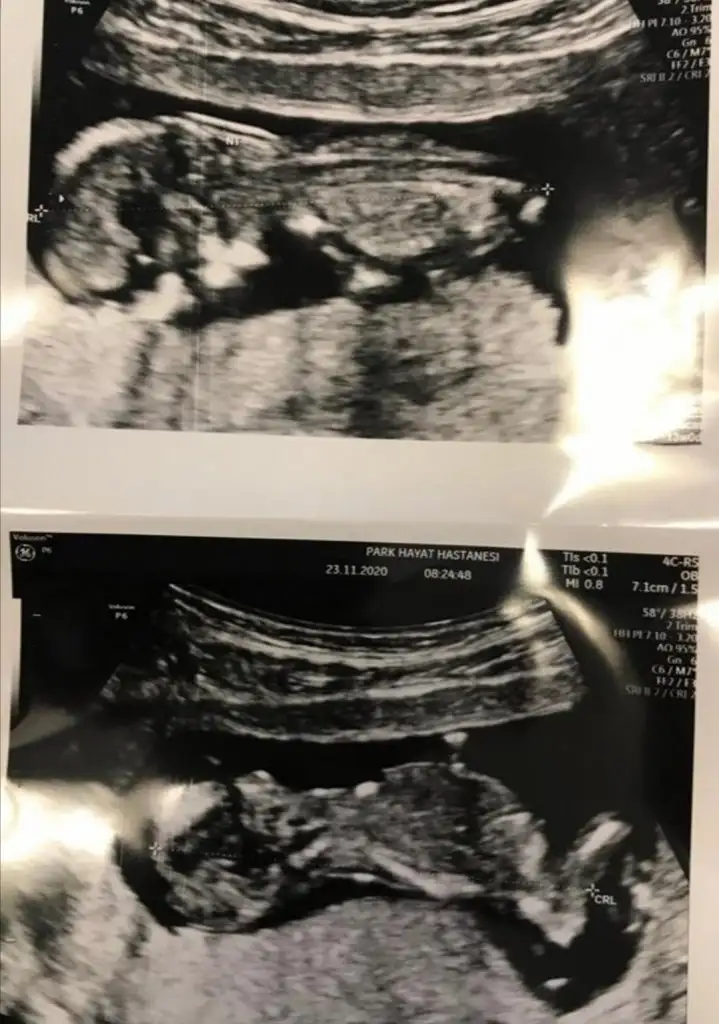

Kız gibi sanki. Başka USG varsa paylaşın emin olamadım

Kız gibi sanki. Başka USG varsa paylaşın emin olamadım![]()

Burada net değil

Burada net değil12 13 olursa paylaşın

USG net değil gördüğüm nub ise erkek sanki kaç haftalık USG

12 haftalıkUSG net değil gördüğüm nub ise erkek sanki kaç haftalık USG